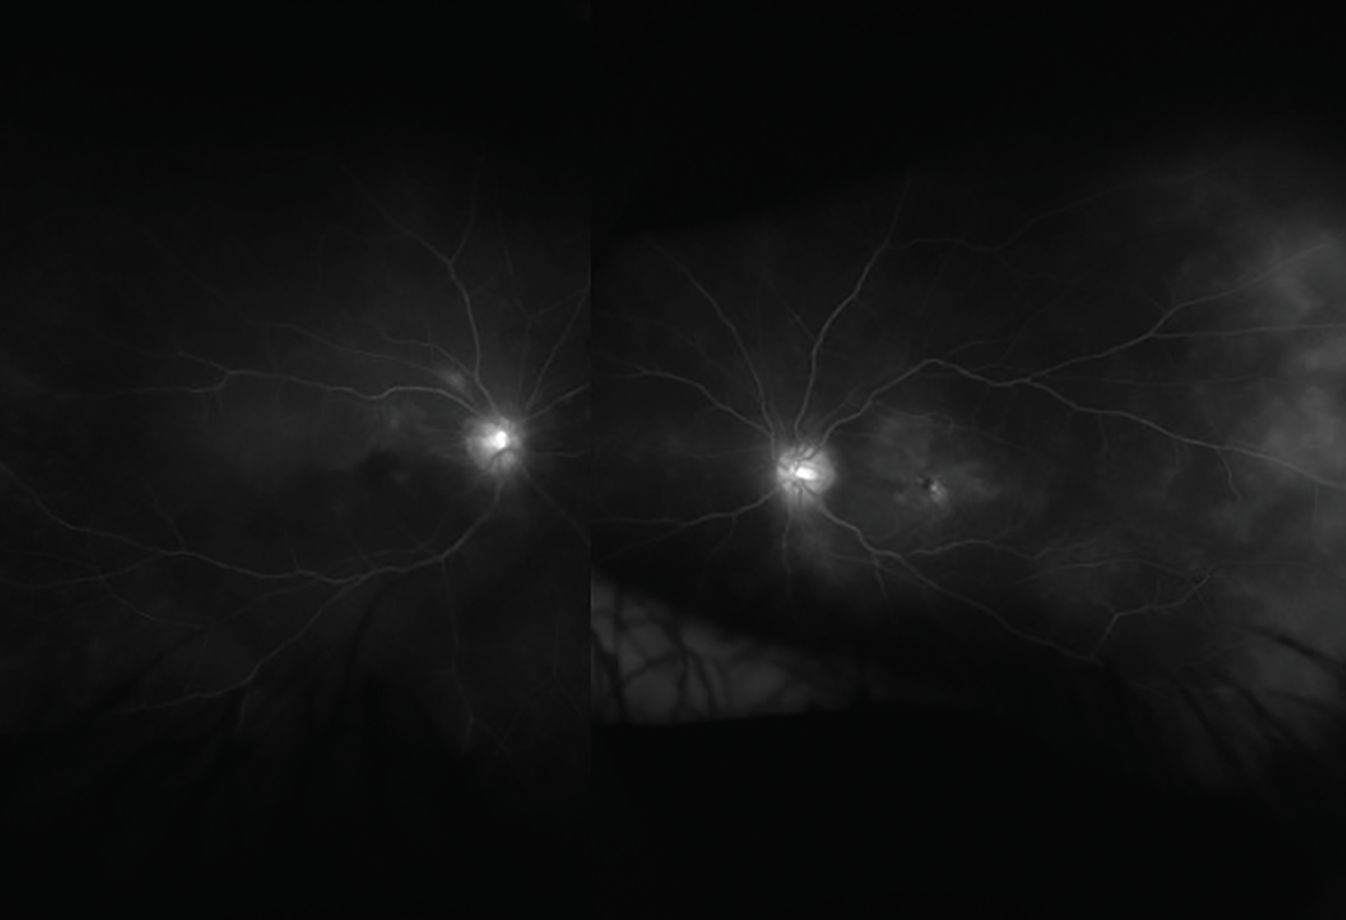

The patient’s ear and nose tenderness, accompanied by worsening ocular inflammation prompted consideration of relapsing polychondritis as a diagnosis. The patient was referred to a tertiary medical center for a uveitis consultation. Fluorescein angiography displayed significant peripheral vascular leakage and dilation of capillaries in all quadrants OU. There was cystoid macular edema in the left eye, confirmed by both by OCT and FA. She was treated with one dose of 1g IV solumedrol followed by 60 mg oral prednisone daily. Her visual symptoms were stable, but she had developed joint pain in her elbows.

Figure 2. Fluorescein angiogram showing extensive macular and peripheral vascular leakage in the right and left eyes. |